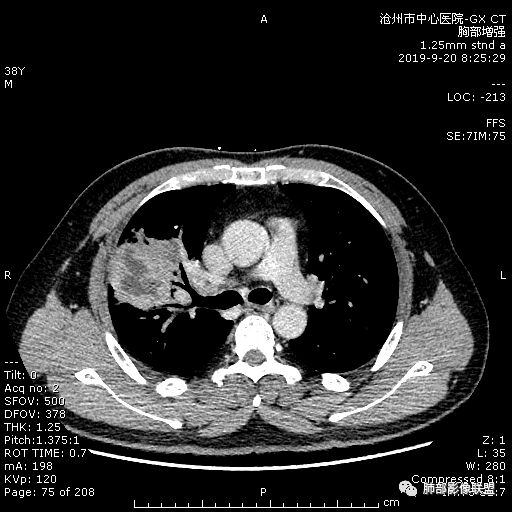

38岁,男性,慢性咳嗽2月,右胸痛8天,无发热;白细胞高,肿瘤标志物不高;右上肺不规则块状影,周围有磨玻璃影,边界清,整体有膨胀感,分叶,与胸膜糊墙,并见栽赃,增强肿块中央坏死,周边强化。综合考虑,考虑恶性,鳞癌可能。

38岁,男性,慢性咳嗽2月,右胸痛8天,无发热。白细胞高,肿瘤标志物不高。右上肺不规则块状影,周围有磨玻璃影,边界模糊,整体有膨胀感,分叶,与胸膜糊墙,可疑栽赃,增强肿块中央坏死,边界清,周边强化明显,强化区有低密度影,壁不规则,跨叶生长,支气管截断,伴支气管扩张,综合考虑腺癌

炎性:延迟强化,病变内气体,糊墙,胸膜增厚;恶性:分叶、收缩;我考虑机化性肺炎并局灶性脓肿,实际工作中把炎性放前面,抗炎复查或穿刺活检除外肿瘤。

南边:

周围GGO,不是远端;

而且这个病灶明显跨段,属于外围的病变,不受某一段支气管的局限;

宽基底,胸膜增厚

炎性病变一定有

但是深分叶,坏死部分内壁不清

近端支气管堵塞

肺门淋巴结肿大

恶性一定不能除外

建议治疗后复查或穿刺,警惕恶性;

为啥说不能排除,而不是直接下恶性?因为有感染的同时很多征象都不是很确定;万一感染掩盖了,或者感染某个过程造成的假象,我们直接下诊断,就没退路了,我觉得应该从写报告的角度去读最合适。

今天病例坏死周围也可以看到明显强化的脓肿壁,只是局部脓肿壁不规则模糊,部分脓肿壁规则清楚。